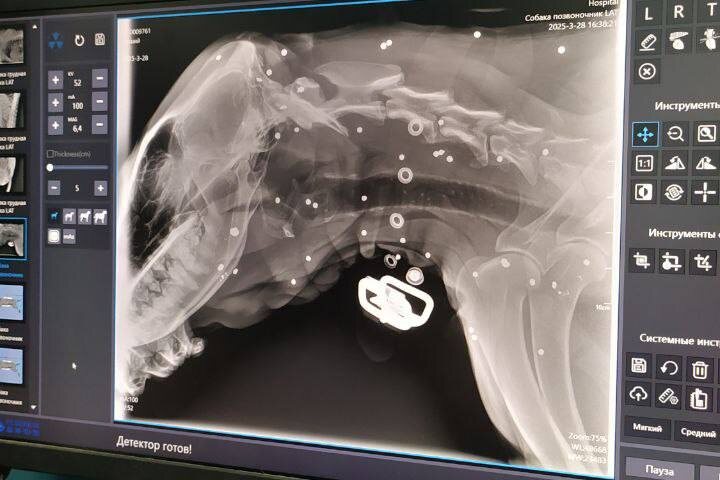

Случаи жестокой расправы над животными продолжают выявлять в Нижегородской области. Не прошло и месяца после жуткой находки у школы на Бору, как сообщения об убийстве собак начали поступать из Семенова. В минувший четверг, 28 марта, местные жители сообщили о двух убитых собаках, брошенных на обочине. Спустя пару дней в местном лесу нашли еще одну умирающую дворнягу. Пес с трудом держал голову, правую переднюю лапу подминал под себя, а на шее у него было множество ран. https://www.nnov.kp.ru/daily/27680/5069504/

Случаи жестокой расправы над животными продолжают выявлять в Нижегородской области. Не прошло и месяца после жуткой находки у школы на Бору, как сообщения об убийстве собак начали поступать из Семенова. В минувший четверг, 28 марта, местные жители сообщили о двух убитых собаках, брошенных на обочине. Спустя пару дней в местном лесу нашли еще одну умирающую дворнягу. Пес с трудом держал голову, правую переднюю лапу подминал под себя, а на шее у него было множество ран.